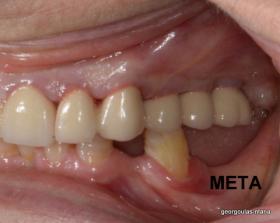

Στην ασθενή αυτή πραγματοποιήθηκε ανοικτή ανύψωση ιγμορείου άνω αριστερά. Σε πρώτη φάση πραγματοποιήθηκε η οστική αύξηση και 6 μήνες μετά τοποθετήθηκαν 3 εμφυτεύματα. Τόσο στην πανοραμική όσο και στην τομογραφία κωνικής δέσμης (CBCT) που πραγματοποιήθηκαν 6 μήνες μετά την ανύψωση είναι εμφανής ο σχηματισμός οστού. Η τελευταία ακτινογραφία και φωτογραφία λήφθηκαν 5 χρόνια μετά την προσθετική αποκατάσταση.